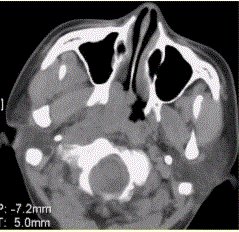

问题 患者男,45岁,鼻塞、涕中带血2周。查体颈部淋巴结增大。专科检查发现,鼻咽腔黏膜肿胀,左侧咽隐窝消失。CT表现如下图。 关于鼻咽癌,表述正确的是

选项 A.以鳞癌居多 B.早期可表现为鼻咽侧壁平坦、僵直、咽隐窝消失 C.常伴囊变或钙化 D.注射对比剂后,肿瘤呈轻度强化 E.对骨的侵犯可为单纯性骨破坏、骨质硬化或两者兼有 F.病变常沿颅底孔道侵犯

答案 ABDEF